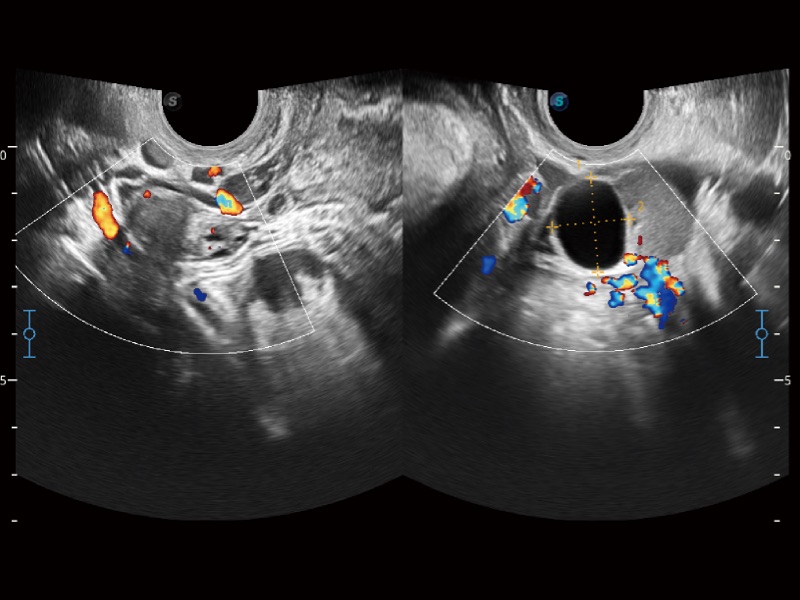

小器官应用

妇产科应用